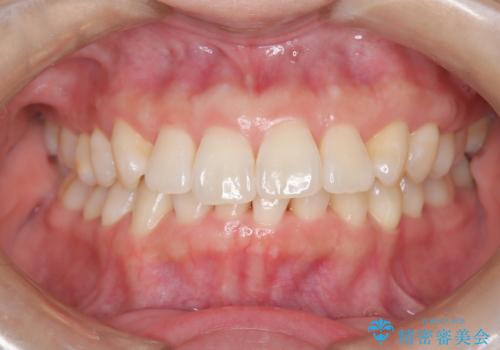

インビザライン ライトパッケージによる部分矯正治療 下の前歯のみの歯並び改善

- インビザライン ライトパッケージパーシャル(下顎のみ)

- 下の前歯の歯並びのみの改善をご希望されました。

インビザライン ライトパッケージ下顎のみ(1枚~14枚まで)での治療を行なっていきました。

マウスピース枚数 初回14枚 + 追加13枚

概ね7ヶ月で治療完了しました。

インビザラインのライトパッケージでは14枚までという枚数制限がありますが、限られた枚数の中で当院独自の工夫を随所に盛り込み、狙い通りの治療結果が得られました。